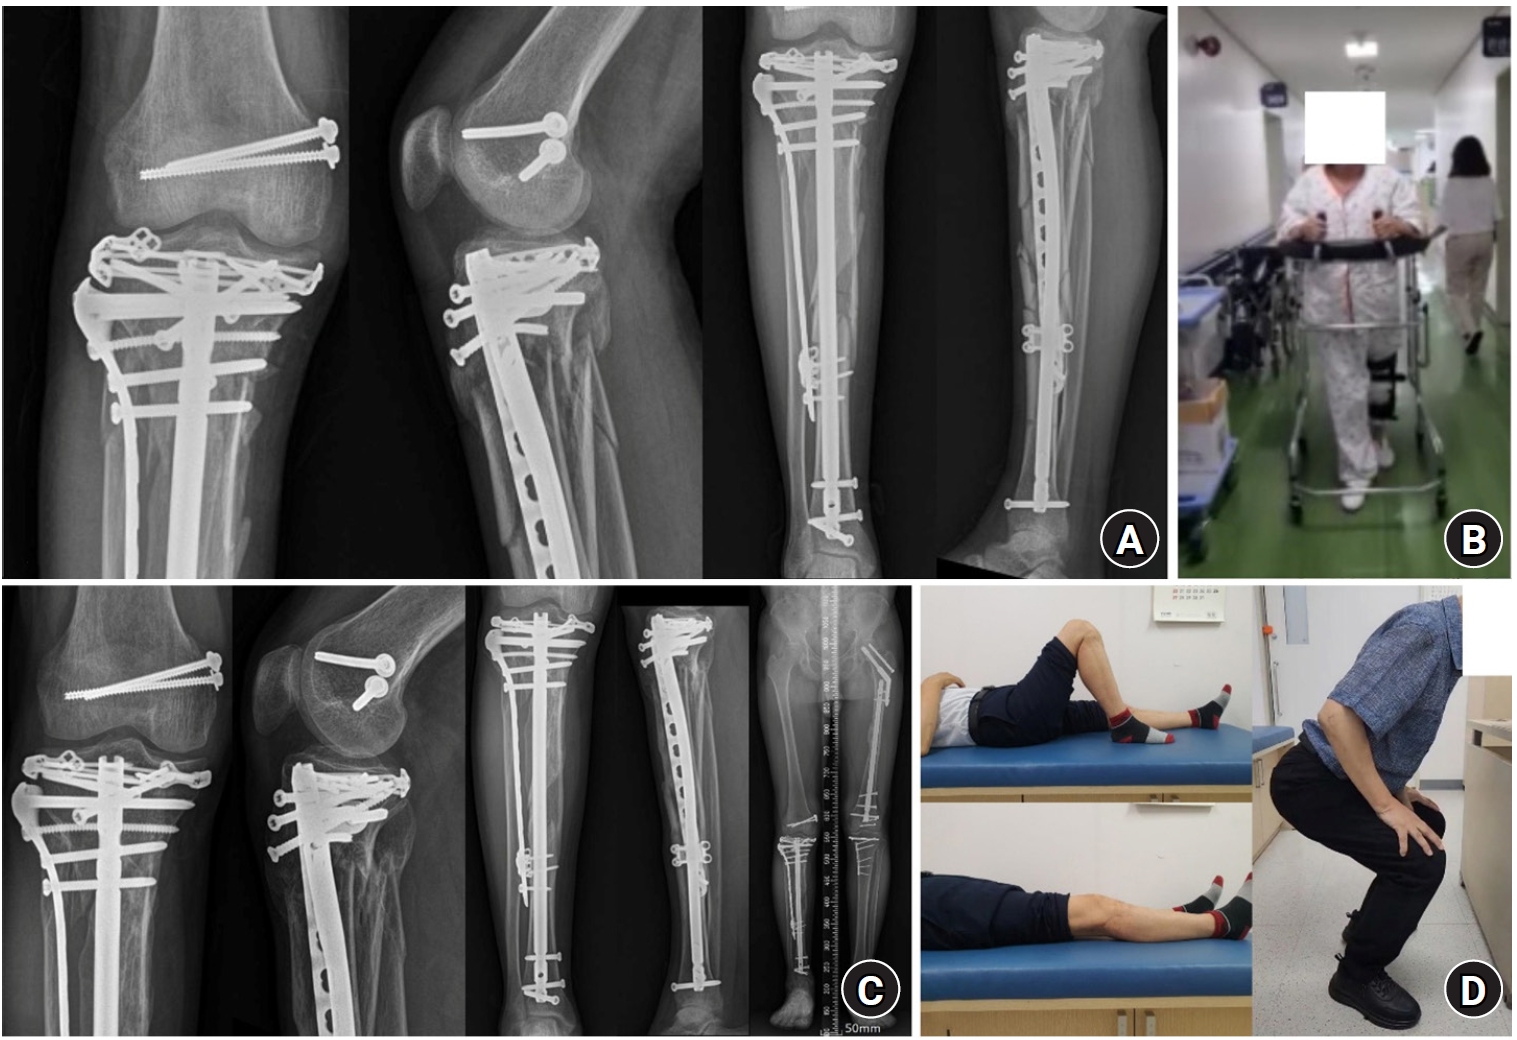

Fig. 7.

Postoperative plain radiograph and computed tomography (CT) images. (A) Postoperative plain radiograph. (B) Coronal and (C) sagittal CT images after fixation.

jmt-2025-00290f7.jpg

Postoperative course following the rim plate-assisted NPC technique

One week later, the left distal radius and ulna and concomitant ipsilateral forearm both-bone fractures were surgically treated, which concluded the surgical procedures. Passive knee range-of-motion exercises were initiated immediately after surgery. Weight bearing and walking ambulation began approximately 4 weeks after surgery, following transfer from the intensive care unit to the general ward. Six weeks after surgery, the patient could walk independently (Fig. 8A and 8B), and bone union was achieved at 6 months. At 9 months, the patient underwent reconstruction of the posterior cruciate ligament to address right knee instability and was subsequently able to return to full physical activity (Fig. 8C and 8D).